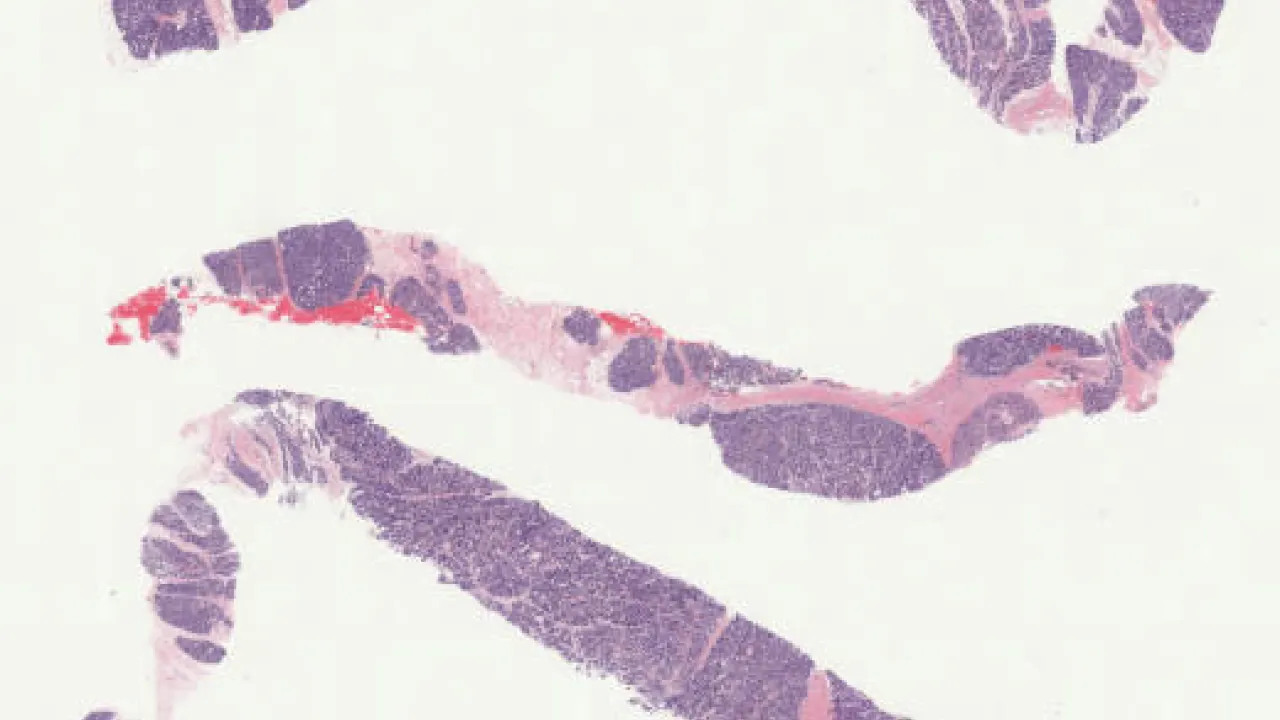

Colon, Pseudomembranous colitis